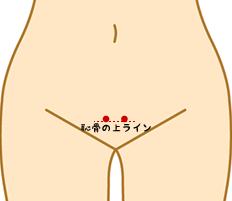

◯恥骨結合の圧痛の有無:

恥骨の場所を正確に↓